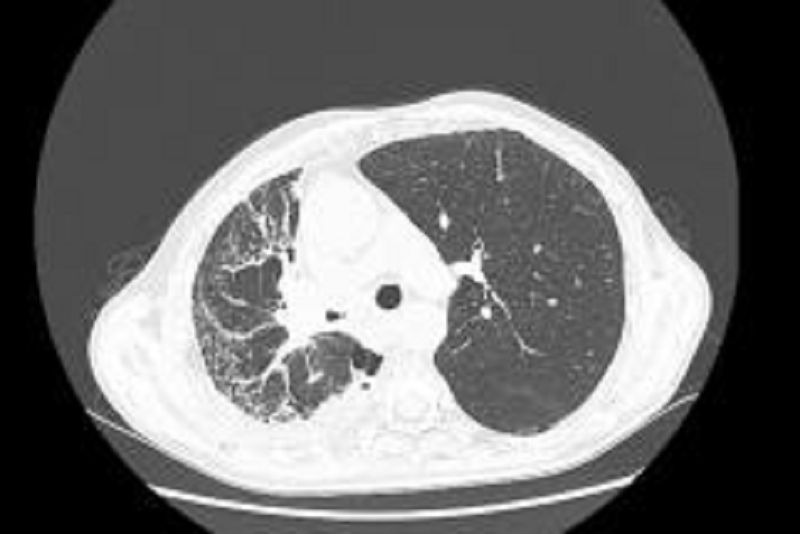

·2018年4月8日,李先生再返院复查,肺部肿块明显缩小。

·2021年3月16日,李先生返院复查,检查结果提示:右肺肿瘤明显缩小,且李先生病情稳定。建议李先生继续服用中药并可回当地医院继续贝伐维持治疗。